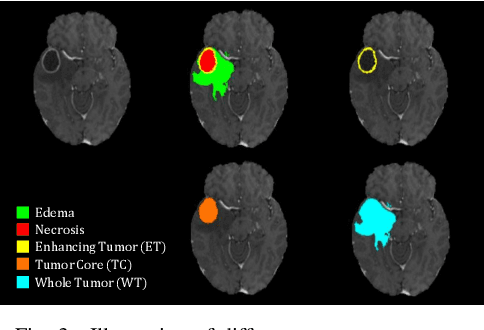

Abstract:Multi-modal magnetic resonance (MR) imaging provides great potential for diagnosing and analyzing brain gliomas. In clinical scenarios, common MR sequences such as T1, T2 and FLAIR can be obtained simultaneously in a single scanning process. However, acquiring contrast enhanced modalities such as T1ce requires additional time, cost, and injection of contrast agent. As such, it is clinically meaningful to develop a method to synthesize unavailable modalities which can also be used as additional inputs to downstream tasks (e.g., brain tumor segmentation) for performance enhancing. In this work, we propose an end-to-end framework named Modality-Level Attention Fusion Network (MAF-Net), wherein we innovatively conduct patchwise contrastive learning for extracting multi-modal latent features and dynamically assigning attention weights to fuse different modalities. Through extensive experiments on BraTS2020, our proposed MAF-Net is found to yield superior T1ce synthesis performance (SSIM of 0.8879 and PSNR of 22.78) and accurate brain tumor segmentation (mean Dice scores of 67.9%, 41.8% and 88.0% on segmenting the tumor core, enhancing tumor and whole tumor).